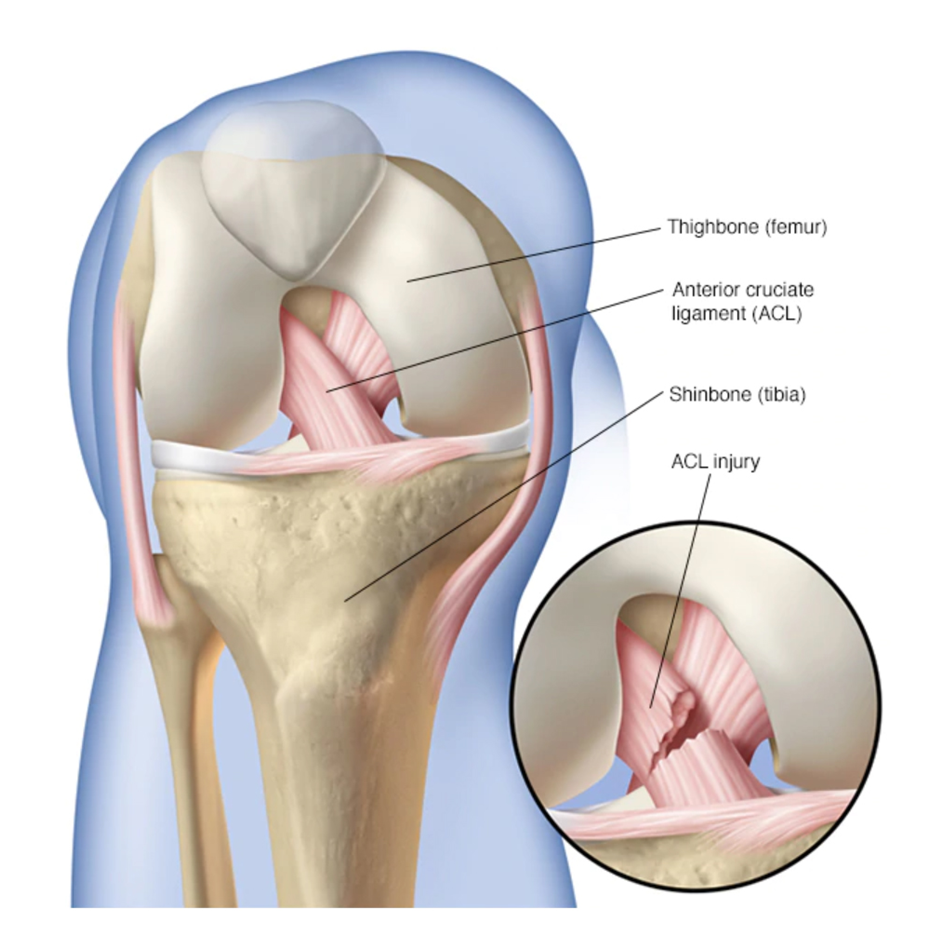

ACL (Anterior Cruciate Ligament) reconstruction is a surgical procedure used to replace a torn ACL in the knee. The ACL is a crucial ligament that helps stabilize the knee joint. When it gets injured, it can cause pain, instability, and difficulty in movement. This surgery is commonly performed on athletes and active individuals who need to restore knee function for daily activities and sports.